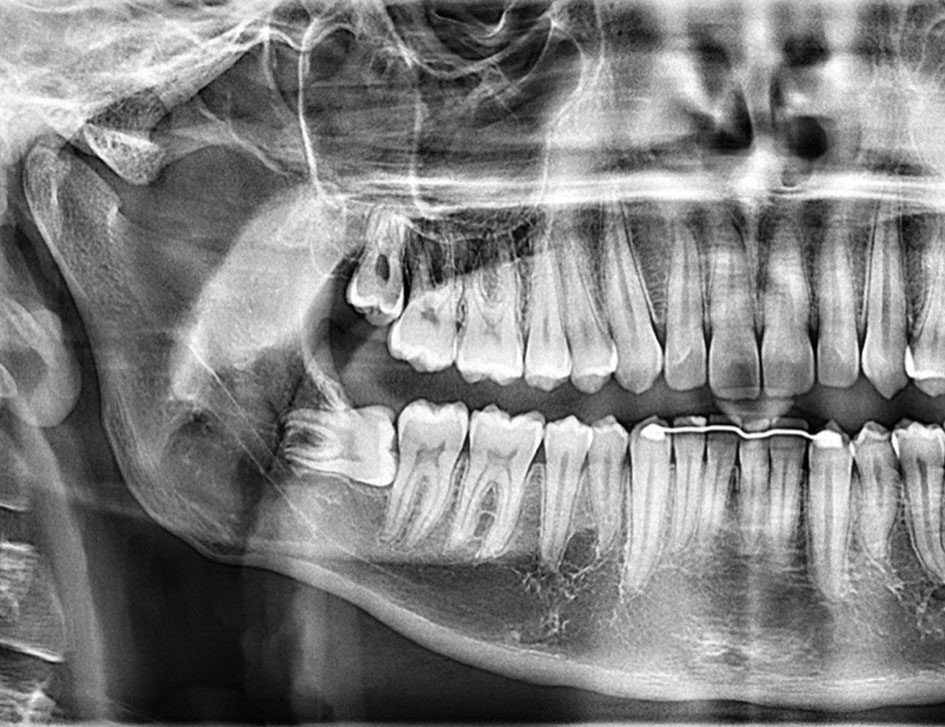

Eine sorgfältige Untersuchung der Zähne, des Zahnhalteapparats und der Mundhöhle steht am Anfang jeder zahnärztlichen Behandlung. Anhand ergänzender Röntgenbilder besprechen wir mit Ihnen verschiedene Behandlungsmöglichkeiten. Darauf basierend erstellen wir für Sie ein individuelles Behandlungskonzept.

Implantate

Implantate dienen nach Zahnverlust als Wurzelersatz. Dazu wird eine Schraube aus Titan oder Keramik in den Kieferknochen eingesetzt. Nach einer Einheilphase kann das Implantat belastet werden und je nach Situation mit einer Krone, Brücke oder als Halte-Element zur Verankerung einer Prothese verwendet.

Orale Chirurgie und Weisheitszahnentfernung

Oralchirurgische Eingriffe, wie Weisheitszahnentfernungen, Wurzelspitzenresektionen, Impalatatoperationen, Knochenaufbauten, Abszessinzisionen führen wir unter örtlicher Betäubung in unserer Praxis durch.